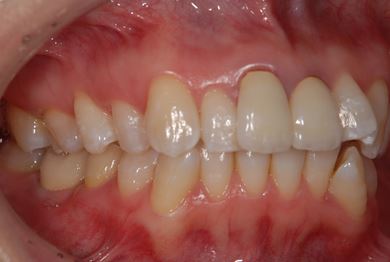

インプラント治療+セラミック治療

| 性別/年齢 | 女性 / 42歳 | ||||||||||||||||||||||||||||||||

| 治療方針 | 右下奥、保存不能の歯を抜歯し、インプラント治療にて、機能的・審美的回復を行う。 | ||||||||||||||||||||||||||||||||

| 治療内容 | インプラント1本、メタルボンドセラミッククラウン2本(メタルボンド用土台1本) | ||||||||||||||||||||||||||||||||

| 総治療費 | 502,740円 | ||||||||||||||||||||||||||||||||

| 治療期間 | 1年3ヶ月 |